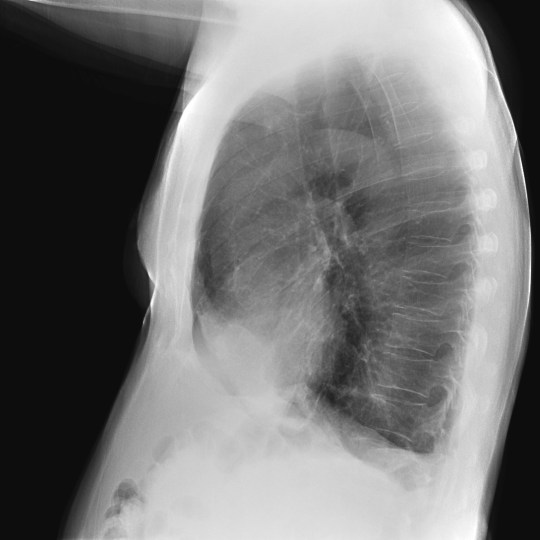

CASO: Febrícula y tos de 4 días de evolución.

Hallazgos:

- En la placa PA se observa una asimetría en los hilios pulmonares, el hilio izquierdo tiene una densidad aumentada.

- Tras examinar la placa lateral se observa un aumento de densidad en la columna que puede ser compatible con una condensación, es el signo de la desnificación vertebral.

SIGNO DE LA DENSIFICACIÓN VERTEBRAL: En la radiografía lateral normal, la densidad de la columna torácica tiende a disminuir desde la parte superior hasta el diafragma; la alteración de ese patrón por la presencia de una densidad superpuesta a la columna, indica la existencia de una consolidación pulmonar. Este signo adquiere especial valor cuando en la proyección posteroanterior la consolidación está oculta en el espacio retrocardíaco o en la base pulmonar.